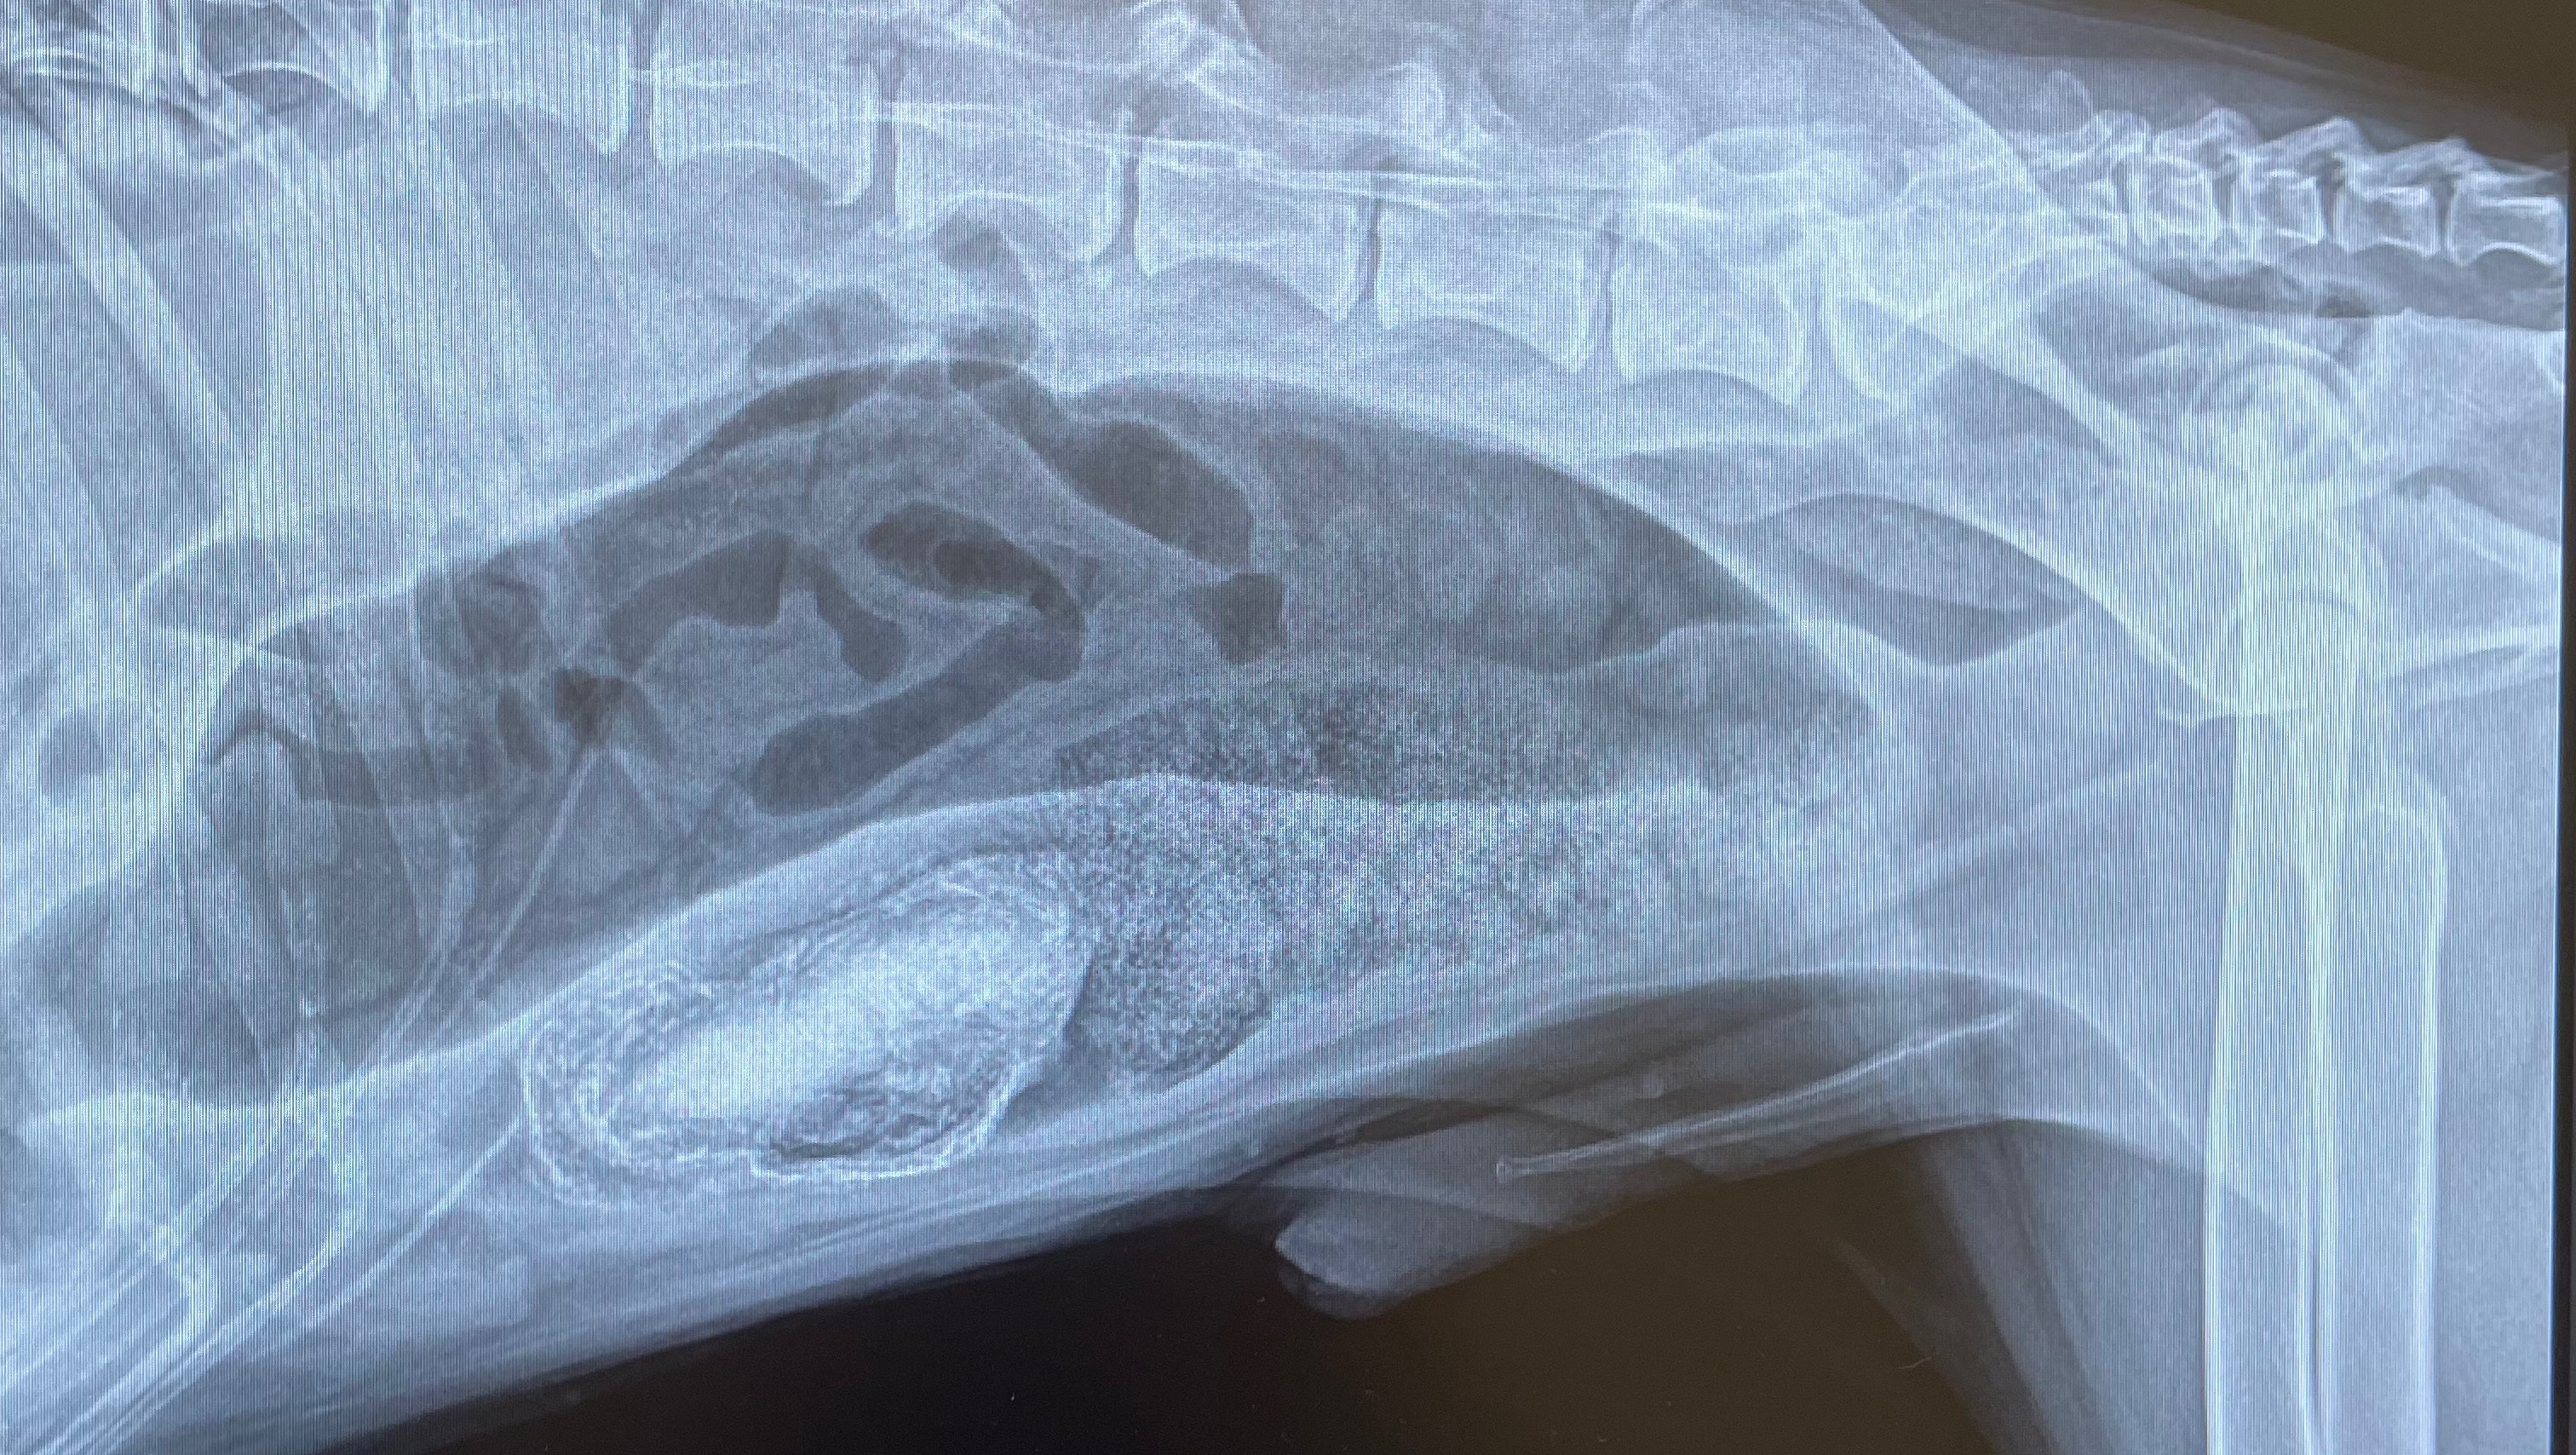

Hi everyone. My dear friends Savannah and her fiance Garrett are going through a really tough time right now with their pup Behr. Within the last two weeks he has developed some really distressing symptoms and stopped eating. After getting several opinions, X-rays and an ultrasound the vets have found that he has, what they expect to be a foreign object, creating a blockage in his intestines. He is very uncomfortable and the only way to save him is to do an emergency exploratory surgery to remove the blockage. Behr is the very best boy (He didn’t even need to be sedated for his imaging because he held so still!) There’s never a good time for something this tragic to happen but over Christmas just makes everything more difficult. Anyone who knows Sav knows that she is a super giving person and her and Garrett will do anything they can to help their boy get through this but they need our help to make it possible! Let’s rally for them and Behr like I know they would for anyone else in this predicament.